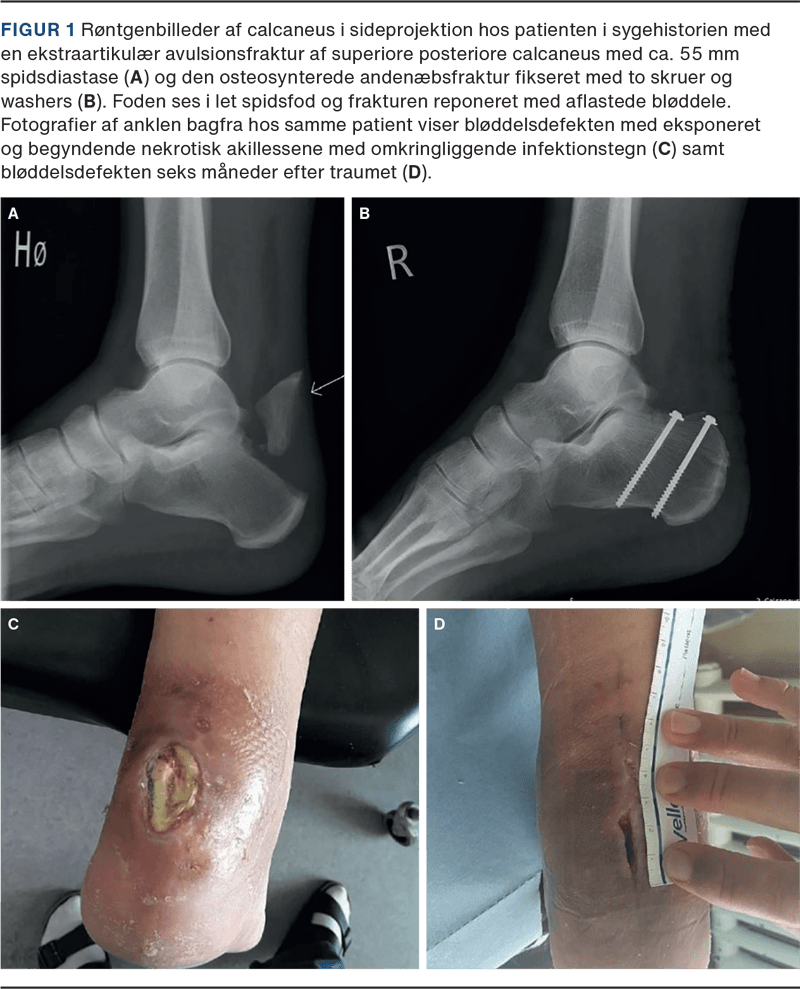

En 71-årig mand henvendte sig i skadestuen to dage efter et mindre vrid i foden ved et fald ned ad få trappetrin. Objektivt fandtes udbredt hævelse lokaliseret om ankelleddet. Distalt for akillessenetilhæftningen blev palperet en ossøs defekt på cirka 2 cm ved tuber calcanei samt ossøst materiale på begge sider af defekten med misfarvet og udspændt hud. Thompsons test var positiv med nedsat plantart fleksionsrespons. Der fandtes ingen øvrige positive fund, herunder ingen sideforskel ved Matles test. På mistanke om ossøs akillesseneavulsion blev der foretaget røntgenbillede af calcaneus, der bekræftede fund af den såkaldte andenæbsfraktur (Figur 1).

Patienten fik anlagt Walker-støvle med tre hælkiler uden tilladelse til at støtte på foden med henblik på at approksimere fragmenterne, slække i trækket fra akillessenen og dermed aflaste bløddelene, og dette blev dokumenteret. Patienten blev indlagt og opereret den følgende dag efter fodkirurgisk konference, hvor det afrevne fragment blev fikseret med to kanylerede skruer, washers og fibertape. Postoperativt var patienten uden støtte i fire uger.

Ved postoperativ kontrol fandtes huden hævet og macereret med epidermolyse. Der blev podet fra det eksponerede område og opstartet behandling med profylaktiske antibiotika. I de følgende måneder voksede defekten sig gradvist større, og patienten undergik multiple, mindre bløddelsrevisioner med vacuum-assisted closure (VAC)-behandling og opfølgning på sårcenteret. Der blev konfereret med plastikkirurgisk og mikrobiologisk afdeling med vejledning i videre behandling vedrørende henholdsvis bløddele og antibiotika. Patienten blev senere indlagt og undergik større operation med fjernelse af osteosyntesemateriale og næsten halvdelen af en avital akillessene (Figur 1). Postoperativt blev besluttet kontinuert antibiotikabehandling i tre måneder med videre sårbehandling.

Seks måneder efter traumet havde patienten fortsat en betydende bløddelsdefekt, men var infektions- og smertefri med gangfunktion (Figur 1).